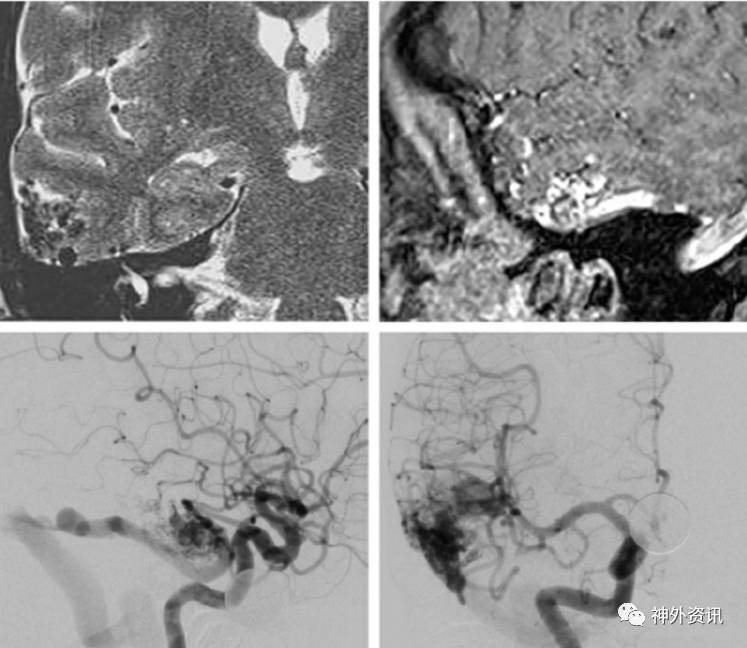

图13. 大型颞叶后内侧AVMs,主要由脉络膜前动脉供血,如图(ICA和椎动脉造影侧位像,上图)。术者采用经皮层、经脑室、经脉络裂的方法(中图)。在穿过颞角的脉络裂中显露脉络膜前动脉 (中图的插图)。AVMs完全游离后,病灶水平的脉络膜前动脉被离断,AVMs去除(下图)。所有浅静脉转为暗蓝色。

图14. 图示另一个颞叶后内侧AVMs。大多数供血动脉源自P2分支(上图)。血肿腔为经皮层入路显微外科操作提供了宽敞的空间。过度增生的P2穿支血管被切断(中图)。移除AVMs (下图)。